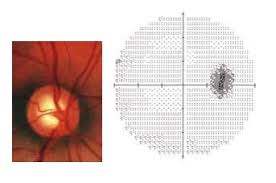

جراحیهای لیزری و غیر لیزری آب سیاه ( گلوکوم)

گلوکوم یا بیماری آب سیاه